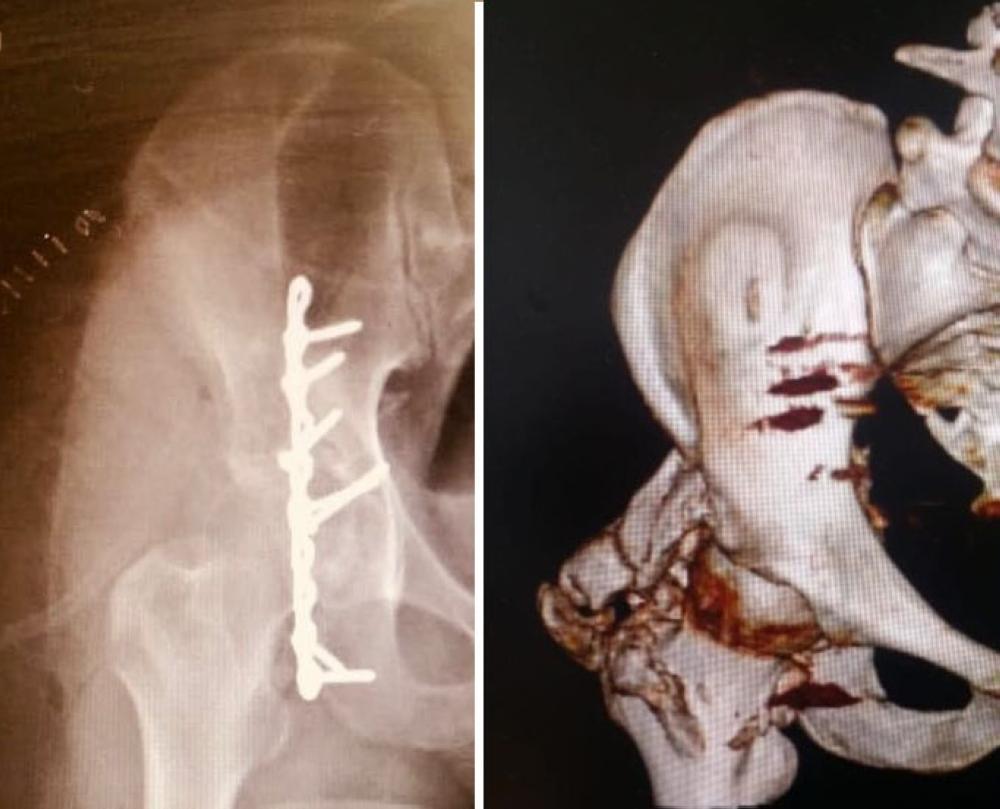

تمكن فريق طبي بقسم جراحة العظام بمستشفى الأمير متعب بن عبدالعزيز بسكاكا من إجراء عملية استئصال تحجر متعدد الأجسام لمفصل الفخذ الأيمن لأول مرة في المستشفى.

وقام الفريق بإجراء تدخل جراحي سريع ومباشر لعلاج مثل هذه الحالات التي تؤدي إلى إعاقة حركة مفصل الفخذ وعدم القدرة على المشي بطريقة طبيعية، حيث تراوح نسبة حدوث التحجر متعدد الأجسام بعد عملية تثبيت كسور الحق بعظام الحوض ما بين 3%-70% خصوصا مع المرضى صغار السن، واستعاد المريض حركة مفصل الفخذ بصورة كاملة بعد العملية.